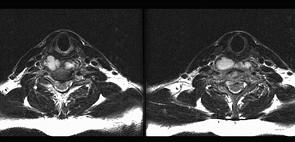

问题 男,38岁,颈部疼痛伴低热1月余,曾有结核病史,结合MRI图像,最可能的诊断是 ( )

选项 A、颈椎骨转移瘤 B、食管异物并感染 C、颈椎体结核 D、咽后脓肿 E、颈椎体结核及咽后脓肿

答案 E